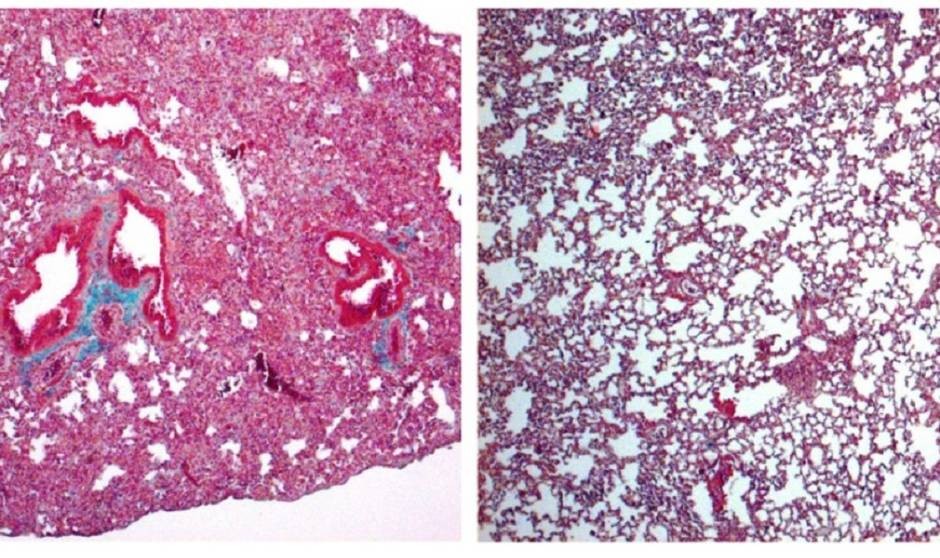

A la izquierda, pulmón de ratón con signos de fibrosis pulmonar grave. A la derecha, pulmón de ratón tratado con cortistatina, en el que el daño es mucho menor./ IPBLN-CSIC

El estudio, publicado en British Journal of Pharmacology, ha demostrado en modelos experimentales preclínicos que la falta de cortistatina provoca una respuesta descontrolada y nociva del sistema inmunitario —la tormenta de citoquinas— y el posterior desarrollo de la reacción fibrótica pulmonar. Por contra, el tratamiento con cortistatina protege frente a las formas graves de daño pulmonar agudo y el síndrome de dificultad respiratoria aguda. Esta característica la convierte en un candidato para tratar la fibrosis más grave causada por Covid-19.